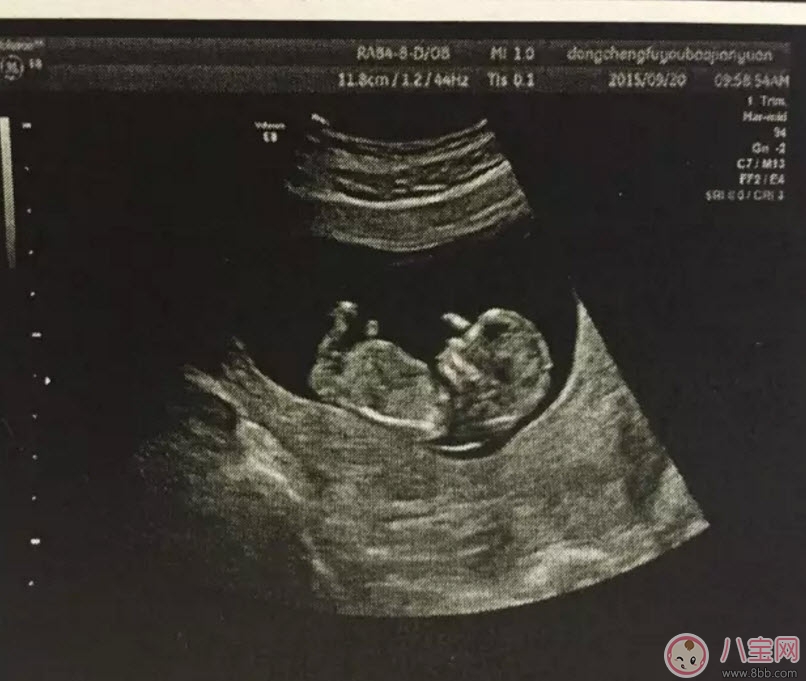

通過(guò)B超能測(cè)出胎兒雙頂徑、頭圍和腹圍等數(shù)據(jù),進(jìn)一步確認(rèn)寶寶的預(yù)產(chǎn)期。還可幫助醫(yī)生觀察胎兒是否存活或有無(wú)畸形,羊水是否過(guò)多等。價(jià)格相對(duì)比較便宜,在90元左右(會(huì)根據(jù)各地具體情況的不同而上下浮動(dòng))。

孕早期的時(shí)候用普通B超就可以了,早期只是檢測(cè)胎兒大概情況,比如檢測(cè)是否在宮內(nèi)、胎兒的頭圍、股骨長(zhǎng)、羊水等指標(biāo)。一般在懷孕8-12周做一次黑白B超確定在宮內(nèi)和胎齡。二維B超適用于孕早期。二維B超是最普通的B超,它采用的是黑白超聲診斷技術(shù),即通過(guò)超聲探頭測(cè)得的是黑白圖像,且只能觀測(cè)到胎兒的組織結(jié)構(gòu),測(cè)量出胎兒頭部、身體的長(zhǎng)度,內(nèi)臟、骨骼的大小和形態(tài),以及是否有畸形。